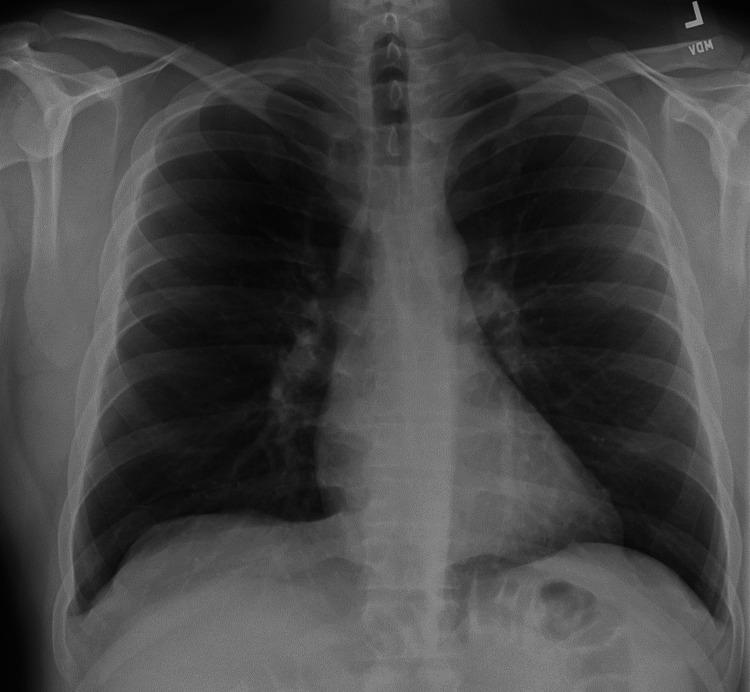

黄甲综合征(YNS)是一种罕见的疾病,其特征为三联征症状:淋巴水肿、指甲变黄和呼吸道表现。它常与慢性咳嗽、支气管扩张、胸腔积液和慢性鼻窦炎等病症相关。尽管其确切病因尚不清楚,但据信淋巴引流受损在其发病机制中起核心作用。YNS主要影响50岁以上的人群,且没有明确的治疗方法,不过一些病例可能会部分缓解或自发缓解。在本报告中,我们介绍了一名35岁左右的男性病例,他有持续咳嗽、鼻窦充血、指甲变黄变形和淋巴水肿的病史一年。包括影像学和肺功能测试在内的广泛检查未发现明显的肺部异常。该患者接受了多轮治疗,包括抗生素、抗真菌治疗、吸入和全身性皮质类固醇以及指甲护理方案,但所有这些治疗均未能有效缓解他的症状。进一步评估,包括牙科影像学检查,发现了牙源性脓肿。拔除感染牙齿后,患者的症状,包括指甲变黄和鼻窦问题,得到了显著且逐渐的缓解。该病例强调了在YNS患者的检查中考虑继发性病因(如牙科感染)的重要性,特别是在标准治疗未能产生改善效果时。据我们所知,这是第一例报告的将牙脓肿确定为YNS潜在病因的病例。YNS与多种全身性疾病有关,包括自身免疫性疾病、甲状腺功能障碍、肾病综合征和恶性肿瘤,但此前尚未记录到与牙脓肿的关联。该病例强调了对YNS潜在促成因素进行全面评估的迫切需求,特别是在不符合典型人口统计学特征的年轻患者中。它还强调了及时处理继发性感染的重要性,这可导致此类病例的显著临床改善。通过说明YNS的一种罕见表现,该病例进一步深入了解了该综合征的复杂性以及牙源性感染在其发展中的潜在作用。